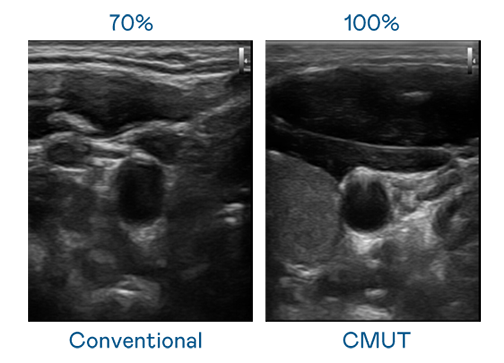

CMUT 技术是一种用电容式微机电元件来产生超音波讯号的技术。与传统 PZT 压电式技术相比,CMUT 频宽增加 30%,更宽频的超音波讯号让影像解析度大幅提升,是实现高影像品质医疗超音波扫描、促进精准医疗发展的关键技术。

大频宽带来超清晰影像

超音波影像的解析度高低,首先取决于探头能发出的讯号频宽。星空体育app官网入口 CMUT 可提供高清晰的超音波讯号,提供高频宽、高灵敏度、影像纹理细节更高的超音波影像,协助医护人员缩短影像判读时间及利用精准的医疗影像进行诊断。